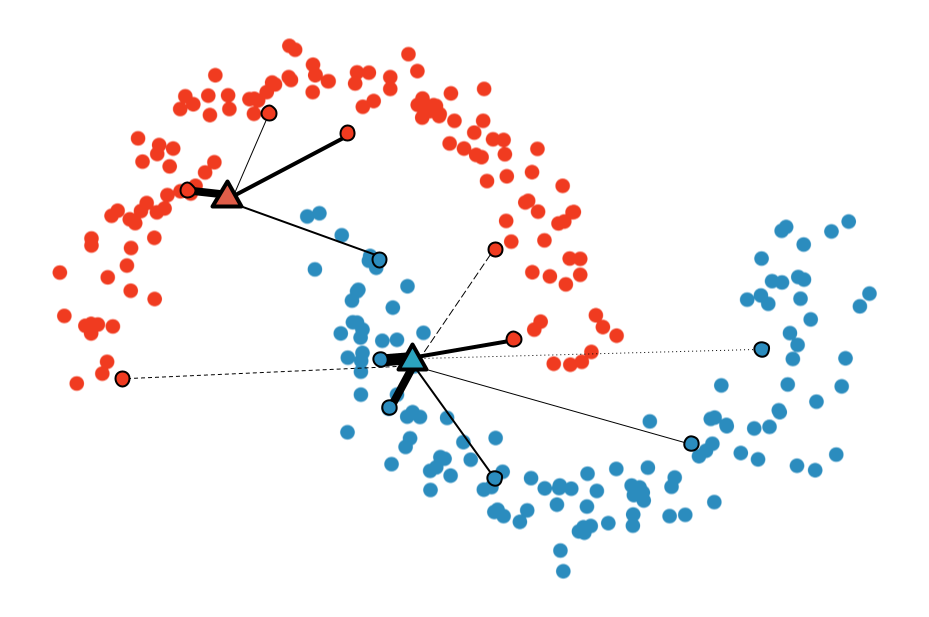

Multi-Sample ζ-mixup: Richer, More Realistic Synthetic Samples from a p-Series Interpolant

Kumar Abhishek, Colin J. Brown, Ghassan Hamarneh

Journal of Big Data, 2024 We propose a generalization of mixup with provably and demonstrably desirable properties that allows convex combinations of more than 2 samples. [Abstract] [BibTeX]

Modern deep learning training procedures rely on model regularization techniques such as data augmentation methods, which generate training samples that increase the diversity of data and richness of label information. A popular recent method, mixup, uses convex combinations of pairs of original samples to generate new samples. However, as we show in our experiments, mixup can produce undesirable synthetic samples, where the data is sampled off the manifold and can contain incorrect labels. We propose ζ-mixup, a generalization of mixup with provably and demonstrably desirable properties that allows convex combinationsof T ≥ 2 samples, leading to more realistic and diverse outputs that incorporate information from T original samples by using a p-series interpolant. We show that, compared to mixup, ζ-mixup better preserves the intrinsic dimensionality of the original datasets, which is a desirable property for training generalizable models. Furthermore, we show that our implementation of ζ-mixup is faster than mixup, and extensive evaluation on controlled synthetic and 26 diverse real-world natural and medical image classification datasets shows that ζ-mixup outperforms mixup, CutMix, and traditional data augmentation techniques.

ζ-mixup: Richer, More Realistic Mixing of Multiple Images

Medical Imaging with Deep Learning (MIDL) Short Paper, 2023 We present a multi-sample Riemann zeta-weighted mixing-based image augmentation to generate richer and more realistic outputs. [Abstract] [BibTeX] [Presentation Slides] [Poster]

Data augmentation (DA), an effective regularization technique, generates training samples to enhance the diversity of data and the richness of label information for training modern deep learning models. mixup, a popular recent DA method, augments training datasets with convex combinations of original samples pairs, but can generate undesirable samples, with data being sampled off the manifold and with incorrect labels. In this work, we propose ζ-mixup, a generalization of mixup with provably and demonstrably desirable properties that allows for convex combinations of N ≥ 2 samples, thus leading to more realistic and diverse outputs that incorporate information from N original samples using a p-series interpolant. We show that, compared to mixup, ζ-mixup better preserves the intrinsic dimensionality of the original datasets, a desirable property for training generalizable models, and is at least as fast as mixup. Evaluation on several natural and medical image datasets shows that ζ-mixup outperforms mixup, CutMix, and traditional DA methods.